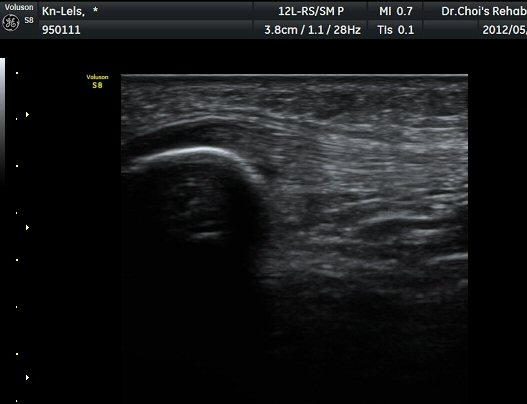

½½°³°ñ¾Æ·¡ ÈûÁÙ Á¾´Ü¸é°Ë»ç¿Í Ⱦ´Ü¸é°Ë»ç¿¡¼­ ÈûÁÙÀÇ ºñÈİ¡ °üÂûµÇ°í(±×¸² 3, 4).

ÈûÁÙÀÇ ºñÈÄ´Â °ÇÃø(±×¸² 5)°ú ºñ±³ÇÏ¸é ¶Ñ·ÈÇϰí, ÆÄ¿öµµÇ÷¯°Ë»ç¿¡¼­ ÈûÁÙ³»¿¡